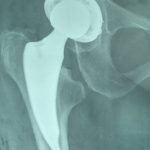

Αρθροπλαστική ΙΣΧΙΟΥ με νέα απλή τεχνική και με κοτυλιαία πρόθεση με ειδικά πτερύγια από βιοεμφυτεύσιμο τιτάνιο, χωρίς οστικό τσιμέντο ή βίδες, για οστεοαρθρίτιδα ισχίου σε Συγγενές Εξάρθρημα ή Δυσπλασία,